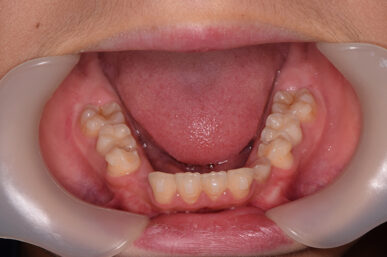

• Before

治療開始が遅くてこのままでは犬歯の生えるスペースが不足していて八重歯になるところでしたが、アライナー矯正で素早く歯を動かして犬歯が生えてくるスペースを作ることで八重歯にならずに済みました。

八重歯のケースは永久歯の抜歯が必要になることもありますが、避けることができました。

矯正後は永久歯がすべて生えるまでは予防歯科で歯の生え代わりと機能を管理します。